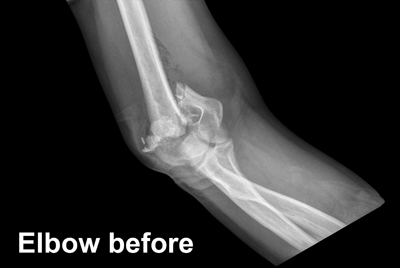

Diagnosis

A healthcare provider will first examine the elbow and surrounding area for signs of a fracture. An X-ray is required to confirm that a fracture is present, and a CT (Computed Tomography) scan might be needed as well in order to get further detail on the injury.